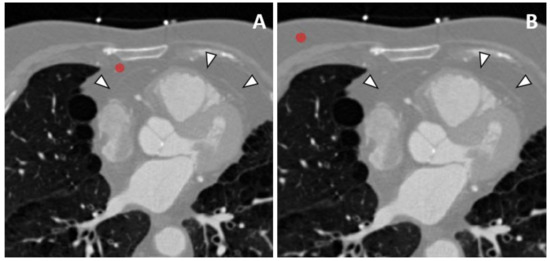

2.3. Image Analysis